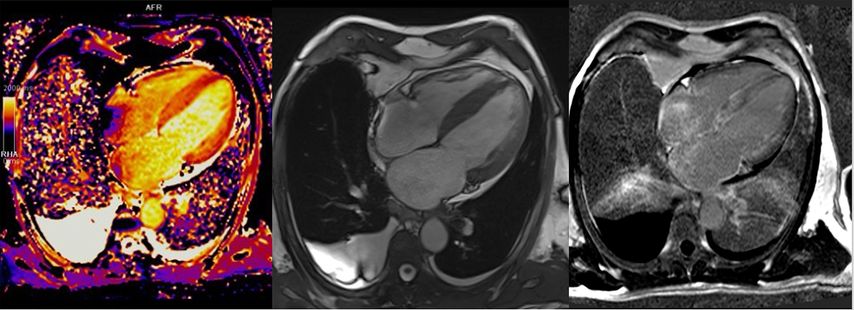

Wenn der Verdacht auf eine zugrunde liegende strukturelle Herzerkrankung besteht, dann ist die kardiale Magnetresonanztomografie (MRT) der Goldstandard zur weiteren bildgebenden Abklärung. In der aktuellen Leitlinie der ESC hat die kardiale MRT-Untersuchung deshalb eine Klasse-I-Indikation im Rahmen der Erstabklärung sowie eine Klasse-IIa-Empfehlung beim Follow-up.11

Neben einer reproduzierbareren Beschreibung der kardialen Geometrie sowie einer exakten Messung der kardialen Funktion ist auch eine Gewebebeurteilung mittels T1- und T2-gewichteten Mappings zur differenzialdiagnostischen Beurteilung der zugrunde liegenden Kardiomyopathie möglich. Mit dem „late gadolinium enhancement“ (LGE) können außerdem Fibroseareale dargestellt werden und in die Risikostratifizierung einfließen. Hier konnte gezeigt werden, dass Patient:innen mit HCM/HOCM und >15% Fibrose des LV oder LVEF<50% ein erhöhtes Risiko für maligne Herzrhythmusstörungen bzw. plötzlichen Herztod (SCD) haben, weshalb eine primärprophylaktische Therapie mit ICD unabhängig von anderen klinischen Charakteristika erwogen werden kann.11

Über die Bestimmung des extrazellulären Volumens (ECV) kann außerdem der Verdacht auf eine Speichererkrankung erhärtet werden (Abb.4). Auch seltene Erkrankungen wie M.Fabry haben charakteristische Befundkonstellationen im kardialen MRT (Tab.1).12

Abb. 4:Kardiale MRT bei ATTR-Amyloidose: erhöhtes T1-Mapping (links), 4-Kammer-Bick mit Hypertrophie (Mitte), diffuses subendokardiales LGE (rechts)